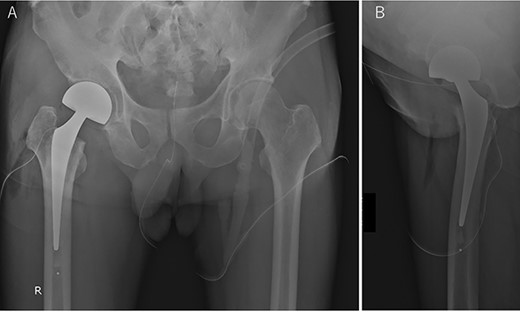

The patient visited our orthopedic surgery department for tumor resection, and cemented hemiarthroplasty (C-stem AMT and SELF-CENTERING Bipolar; Depuy Synthes, Warsaw, IN) was performed (Fig. 3A and B). The tumor could not be identified grossly from the articular surface and the femoral head was sliced and cross-sectioned. The boundaries of the tumor were not clear to the naked eye, and the boundaries could only be inferred in conjunction with the imaging findings (Fig. 4A). The size was approximately 18 × 13 mm. Pathologically, the tumor cells were spindle-shaped, with no nuclear atypia, and showed cotton mass-like calcification (Fig. 4B). Immunohistochemically, tumor cells were positive for CD56, ERG and SATB2. The diagnosis was spindle to round cell tumor, most likely a phosphaturic mesenchymal tumor (PMT). One month after tumor removal, the serum phosphorus concentration and %TRP increased to 3.3 mg/dL and 89.3%, respectively, when compared with the preoperative level, and the FGF23 concentration decreased to 25.4 pg/mL, and was within the normal range. At 9 months postoperatively, the patient’s back pain and fatigue had improved and he was able to walk without a cane. There were no specific symptoms in the right hip joint, and X-ray radiography showed no changes. At that time, FGF23 was 28.0 pg/mL, which was within normal range.

Postoperative anterior–posterior radiographic view of the both hip joints (A) and lateral view of the right hip joint (B).